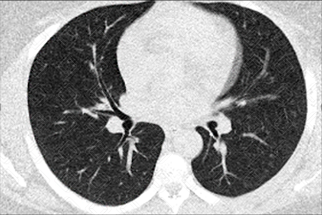

Texto alternativo para a imagem Figura 1. Créditos: Dra. Elazir Mota - Rio de Janeiro/RJ

Descrição das figuras: Tomografia computadorizada do tórax, cortes nos planos axiais, nas janelas de pulmão (onde se visualiza a doença do parênquima pulmonar) e na janela de partes moles (onde se observa o mediastino e suas estruturas, como presença de linfonodomegalias, massas mediastinais, coração e vasos da base).